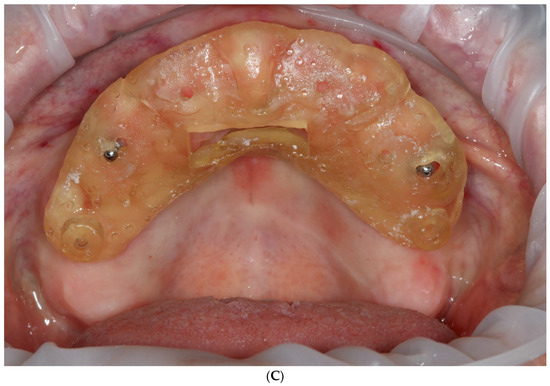

- Extraction of remaining teeth, immediate temporary implant placement, and removable denture delivery.

- Those printed on a desktop 3D printer (Phrozen mini 4k, Phrozen Tech. Co., Ltd., Hsinchu City, Taiwan) [6];

- Those printed and fixed with a rigid welded bar, as a reinforced overdenture shows a lower risk of fracture, when compared to that associated with nonreinforced dentures [25];